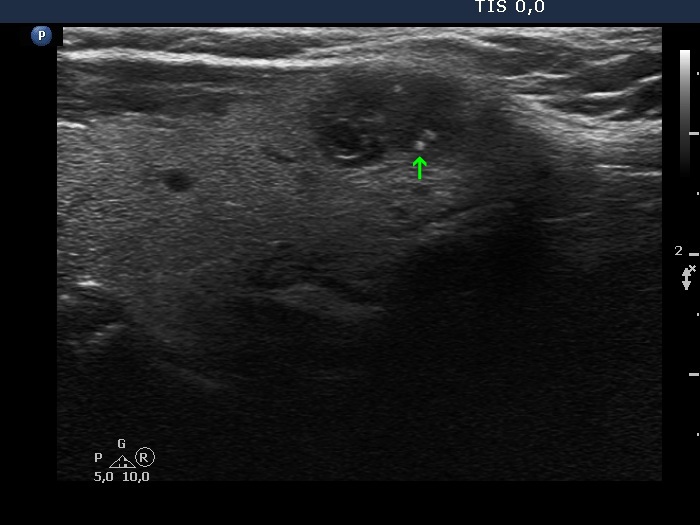

The borders of the nodule - case 2069 (ultrasonographic picture 3b)

Left lobe, another longitudinal scan. The origin of the hyperechoic granules is obscure. The most dorsal one (marked with green arrow) is prebably composed of two punctate echogenic granules (microcalcifications).